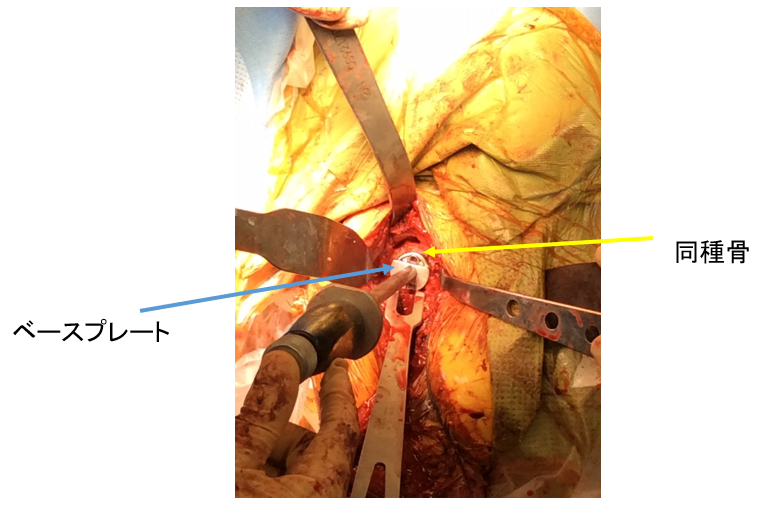

そこで採型した同種骨をベースプレートにつけて、変形した関節窩に適合させます

採型した同種骨をベースプレートにつけて、変形した関節窩に適合させます

関節窩に、同種骨のついたベースプレートを固定します

関節窩に、同種骨のついたベースプレートを固定